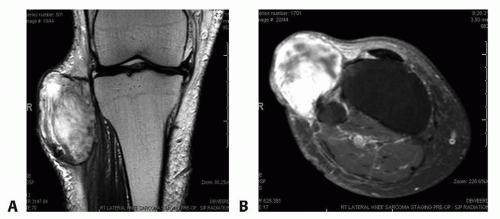

FIG 1 • A. Coronal and axial (B) MRIs demonstrating a high-grade soft tissue sarcoma abutting the proximal tibia and knee joint.

Magnetic resonance imaging is the modality of choice for soft tissue tumor evaluation (FIG 1A,B).